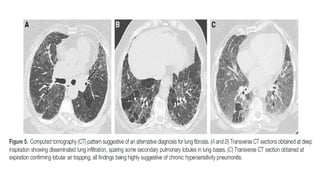

(A) peripheral consolidation and air bronchograms, (B)bronchocentric

distribution

© Consolidation, with more central ground-glass opacity, corresponding to the

reversed halo sign

(A) peripheral consolidationand air bronchograms, (B)bronchocentric distribution © Consolidation, with more central ground-glass opacity, corresponding to the reversed halo sign